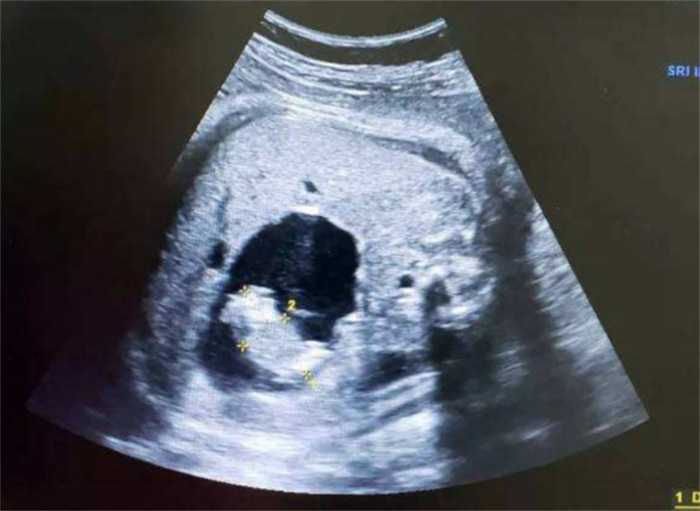

“你肚子里的的确是个婴儿,你看她的手还在动!”县医院的医生拿着检查结果,一本正经地告诉浦志强。

医生在手术室内忙碌了4个小时,帮助浦志强产下了一名女婴。女婴足足有18斤重,刚出生时还有呼吸,但很快就失去了生命体征。

在查阅过海内外各种资料后,医生判断,浦志强可能患上的是一种名为“寄生胎”的先天性疾病。这种疾病发病率极低,仅有五十万分之一。

那什么是寄生胎呢?拿浦志强来说,当年他还是母体内的一个胎盘的时候,他有一个同胞的妹妹。浦志强的生命力比妹妹顽强,不断“吞噬”妹妹的胎盘,导致母亲只生下来他一人。

浦志强出生时,体内还带有妹妹的胎盘,随着他的成长,妹妹也在他的体内不停发育,导致他的肚子越来越大。到2003年,妹妹已经长到了18斤重,导致浦志强不堪重负,才出现了腹痛晕倒的状况。

妹妹以“肿瘤”的形式在浦志强的体内生活了31年,从他的体内被取出后,因为失去了寄生环境,很快就死亡了。